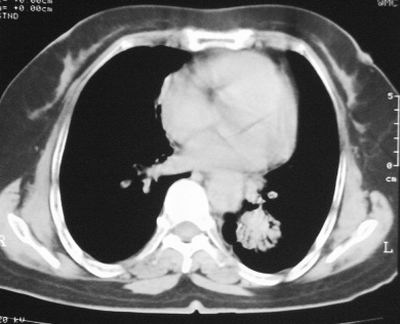

左下肺癌伴左肺门淋巴结转移

支持考虑左下肺原发性肺癌,并左肺门淋巴结肿大

左下周围型肺癌伴左肺门淋巴结及右肺转移可能性大.

左下肺后基底段实性肿块,周围有毛刺,病变周围有肺气肿,与降主动脉间有条带状影相连,病灶4年前查体发现,纵隔内未见肿大淋巴结。考虑.肺隔离症,建议增强扫描与周围型肺癌鉴别。